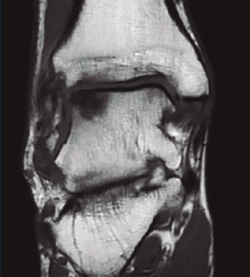

Un paciente presentaba lesiones de cartílago considerables a nivel de la cúpula astragalina secundarias a la afección sinovial que se trataron con legrado y perforaciones (Figuras 2 y 3).

Figura 3. Artroscopia anterior realizando perforación de la lesión condral tras la limpieza previa.